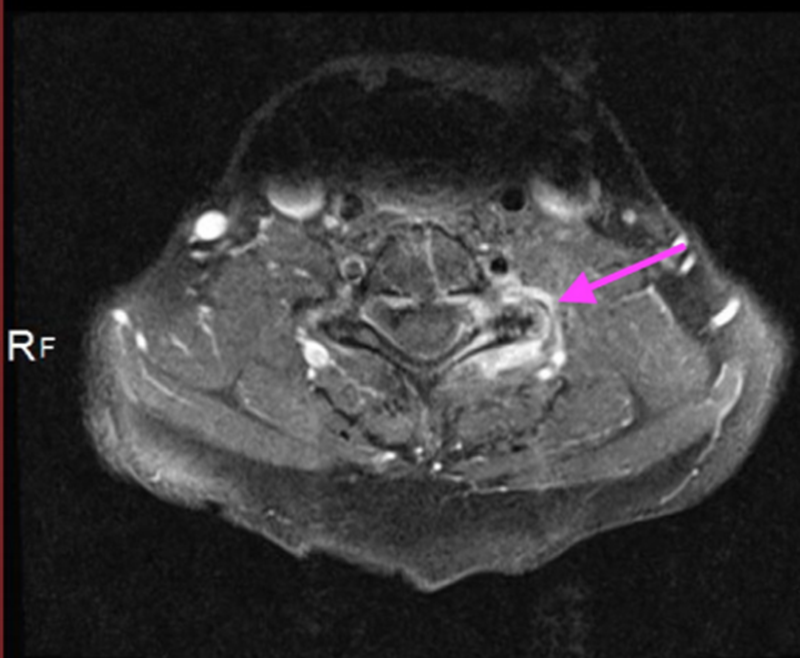

焦磷酸钙沉积疾病致急性脊髓压迫

A、注射钆前轴位T1加权MRI扫描显示硬膜囊背侧有低信号钙化肿块移位;B、注射钆后,低信号区周围可见强化环;C、矢状位T2加权MRI图像。箭头显示侧隐窝内有囊性肿块